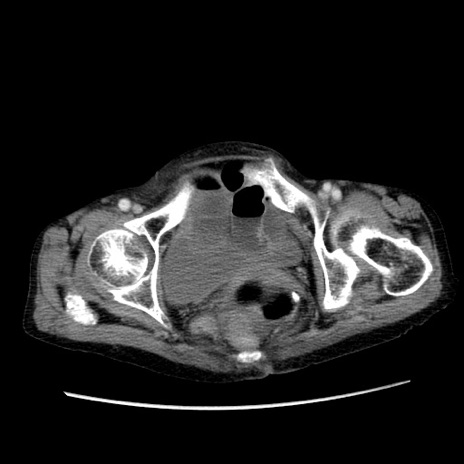

冠状断像

【症例】80歳代女性

【主訴】胸のつかえ感

【現病歴】約9時間前に食後から胸のつかえた感じあり、嘔吐あり、来院。

【既往歴】胃癌(全摘)、胆摘、虫垂炎

【身体所見】心窩部に圧痛あり、反跳痛なし。

【データ】WBC 5700、CRP 0.05